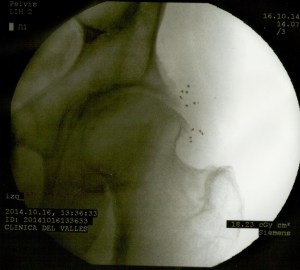

A continuación las imágenes de radioscopía que corresponden al paciente en cuestión. Se observan en primer lugar la colocación de las agujas que vehiculizan los microimplantes, y éstos (pequeños puntos) ubicados próximos a la ceja cotiloidea y a la osteofitosis de la cabeza del fémur.